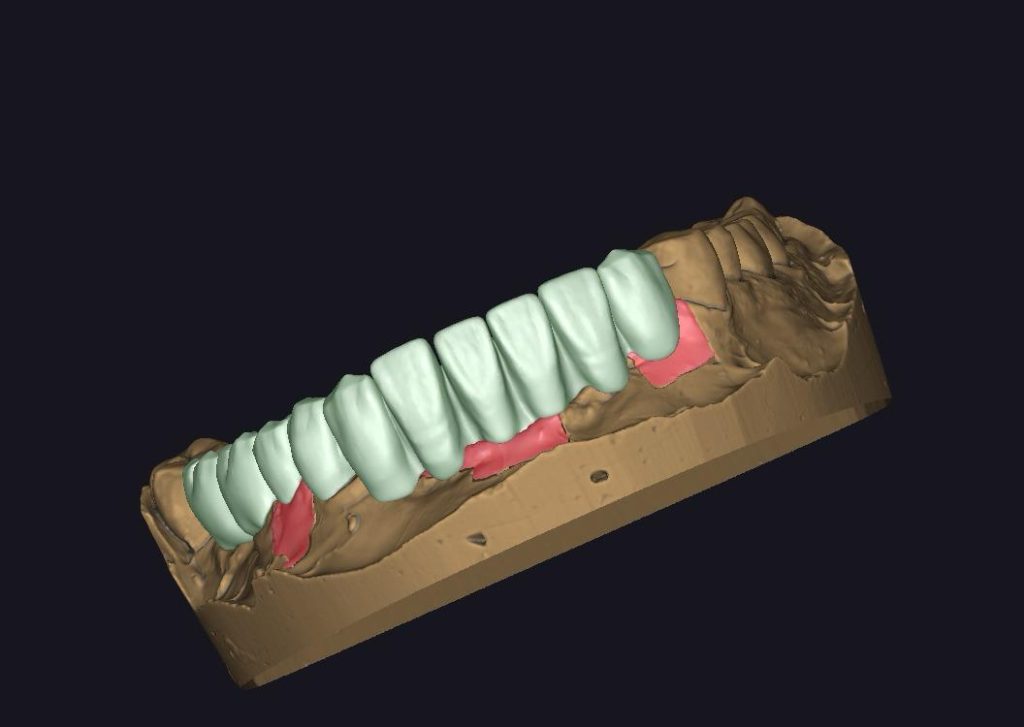

ZIRKONYUM POSKOR

ZİRKONYUM MARYLAND

ZIRKONYUM INLEY ONLEY & LAMINATE

ZIRKONYUM RICHMOND